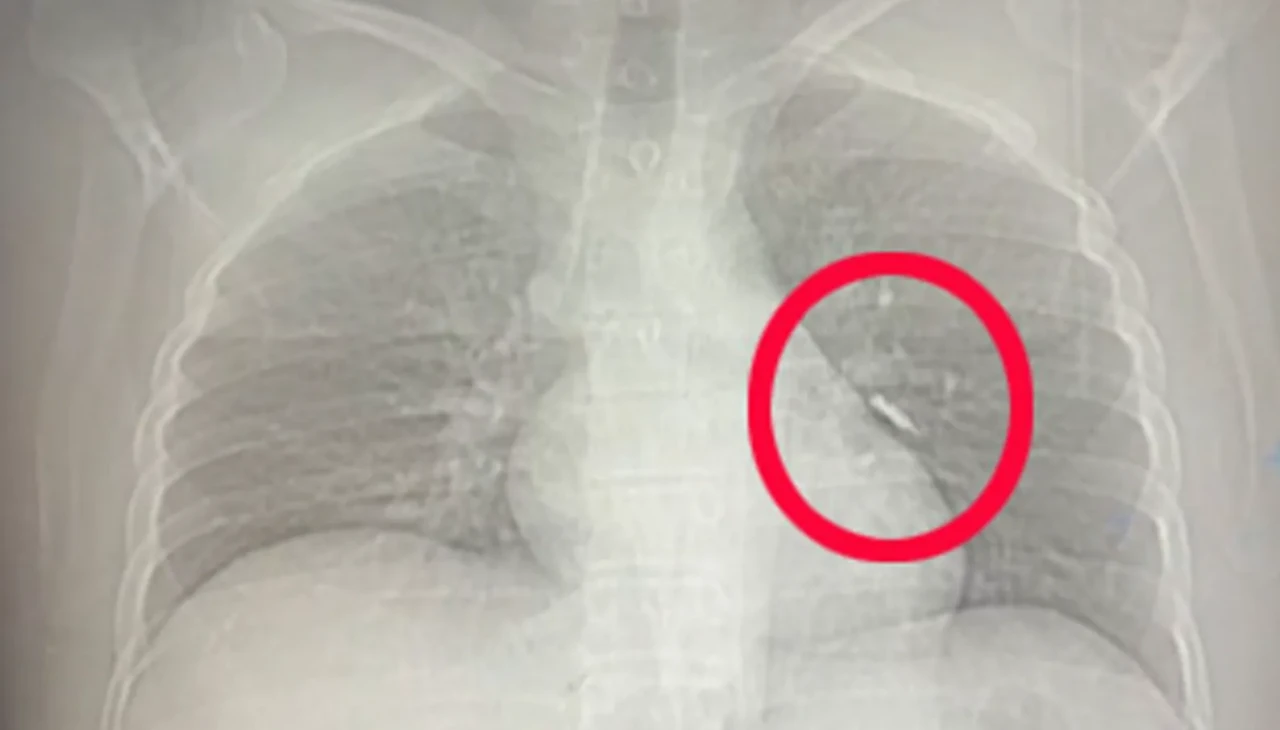

İmplant vidası, yapılan ilk kontrollerde hastanın sol akciğerinde, bronşların derin bir bölümüne saplanmış halde bulundu. Solunumu tamamen engellemeyen bu durum, yine de müdahale gerektirecek düzeyde tehlikeliydi.

Van Eğitim ve Araştırma Hastanesi’ne sevk edilen hasta, göğüs cerrahisi ekibinin gerçekleştirdiği uzun süren bronkoskopi müdahalesine alındı. Ancak vida yerinden oynatılsa da çıkarılamadı. Operasyonun ardından beklenmedik bir gelişme yaşandı: Hasta, geçirdiği şiddetli öksürükle birlikte implant vidasını midesine gönderdi. İlerleyen saatlerde, vida doğal yollarla vücuttan atıldı.